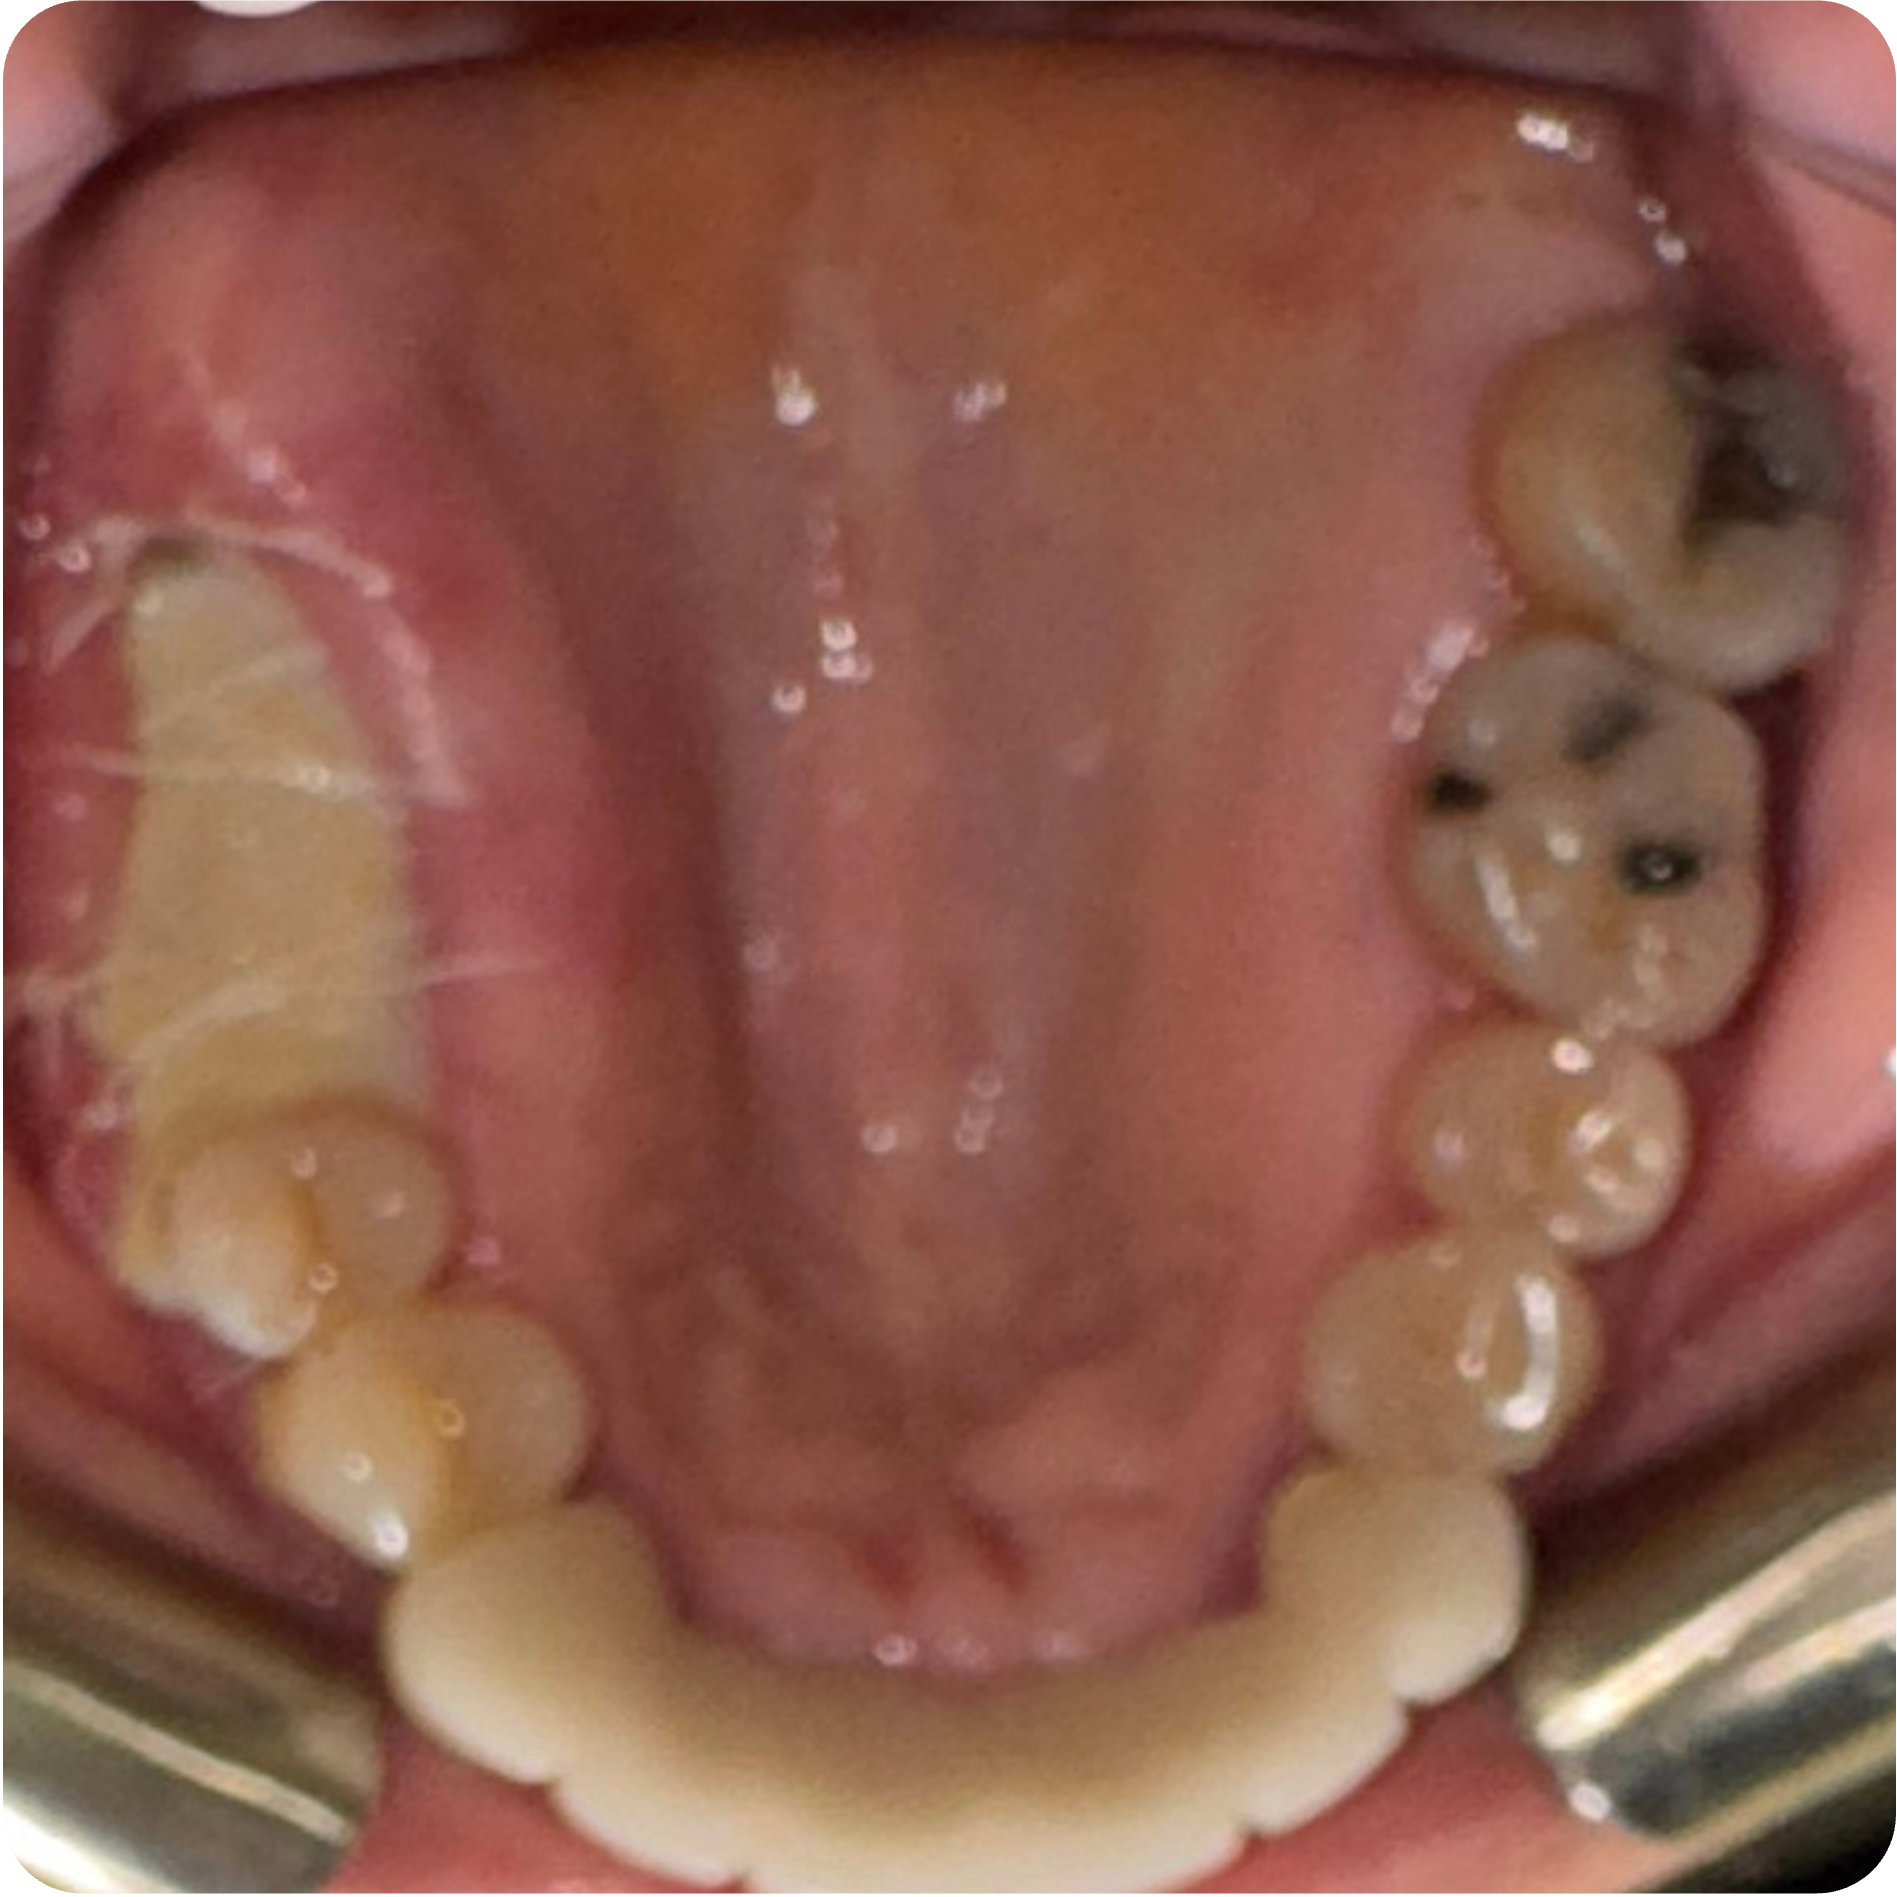

Visual Case Progression

All clinical images are shown at a consistent size for easy comparison.